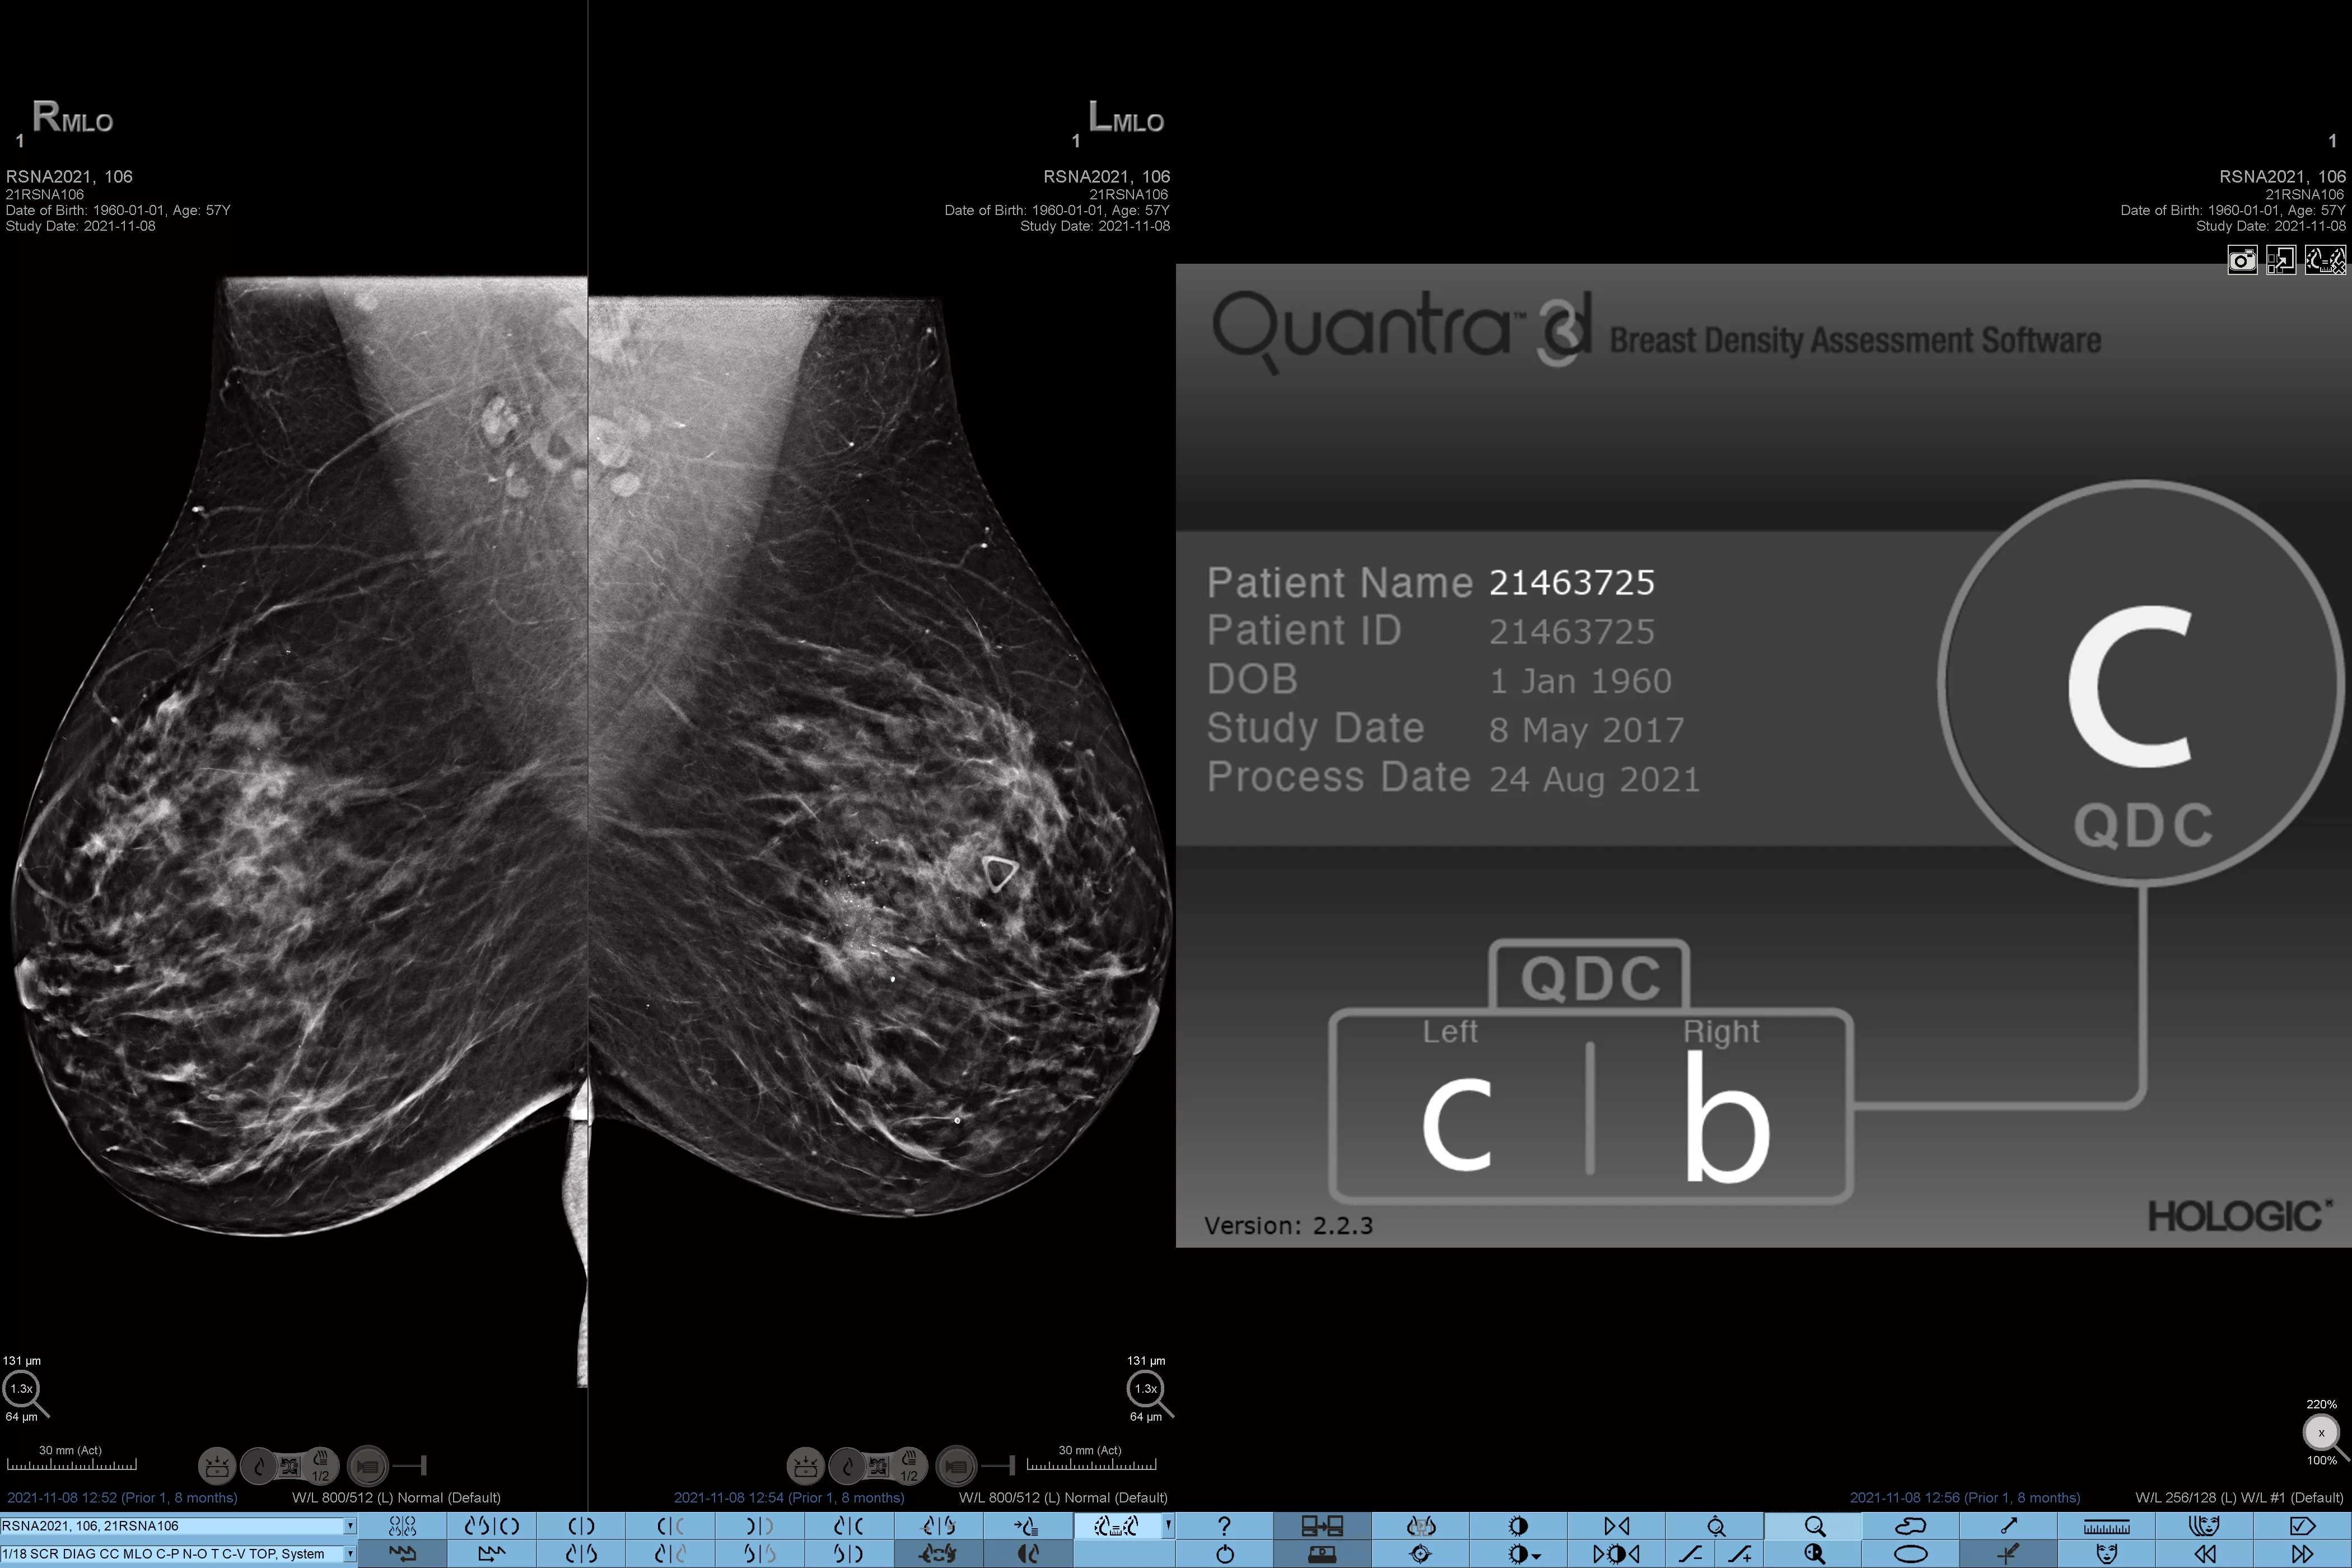

Sabe-se que uma maior densidade mamária aumenta o risco de desenvolver cancro da mama.1 Consequentemente, é fundamental uma análise precisa e não enviesada. O software de tecnologia Quantra, com aprendizagem automática, analisa a distribuição e a textura do tecido parenquimático, tanto através de imagens de 2D™ como de tomossíntese. Este categoriza a mama em quatro categorias de composição da mama, em conformidade com as diretrizes da American College of Radiology (ACR) BI-RADS Atlas 5th Edition.2

Algoritmo de aprendizagem automática objetivo que define a categoria de densidade mamária com base na análise da textura e do padrão do tecido mamário.

*Os resultados baseiam-se nas categorias ACR BI-RADS, em conformidade com as orientações revistas da American College of Radiation (ACR) BI-RADS Atlas 5th Edition. Tal tem em conta o padrão e a textura, comparativamente ao volume, ao determinar a densidade.